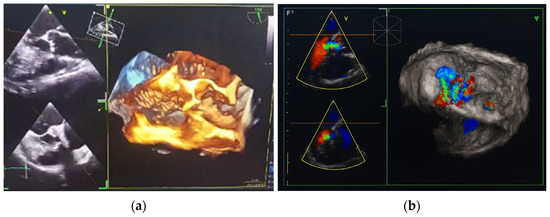

Figure 3.

Transesophageal heart ultrasound 3D imaging. (a) 3D reconstruction of the aortic root and ascending aorta. (b) 3D Color Doppler imaging of aortic regurgitation.

In October 2024, the patient was admitted to our Division of Rheumatology and Immunology due to exacerbation of her underlying overlap syndrome, demonstrating moderate to high disease activity: Disease Activity Score 28-ESR was 4.95 and Systemic Lupus Erythematosus Disease Activity Index was 6. Clinical symptoms included continuous moderate chest discomfort and worsening dyspnea upon exertion. She denied gastrointestinal or respiratory complaints, fever, or systemic signs of infection. Her long-term pharmacotherapy regimen included prednisone 7.5 mg/day, pantoprazole 40 mg/day, atorvastatin 20 mg/day, cholecalciferol 20,000 IU weekly, furosemide 40 mg/day, and lercanidipine 10 mg/day. Vital signs on admission were stable: blood pressure 140/90 mmHg, heart rate 76 bpm, and temperature 36.7 °C. Cardiovascular auscultation revealed a grade 2/6 systolic murmur over the precordium. Musculoskeletal examination was notable for bilateral wrist synovitis, bilateral shoulder pain with restricted range of motion, right knee arthralgia with limited mobility, and fixed flexion deformities of the right-hand fingers and left elbow. There was no clinical evidence of peripheral edema. Laboratory evaluation revealed: leukocytes 6500/µL, hemoglobin 88 g/L, platelets 188,000/µL, C-reactive protein (CRP) 11.7 mg/dL, erythrocyte sedimentation rate (ESR) 50 mm/h, hypocomplementemia (low C3 and C4), serum urea 4.9 mmol/L, and serum creatinine 144 µmol/L. Immunological testing showed negative RF and ACPA. Antinuclear antibodies (ANA) were positive at a titer of 1:160 with a homogeneous nuclear staining (AC-1 pattern). Anti-dsDNA was markedly elevated (86 IU/mL), and antiphospholipid antibodies (aPL), including lupus anticoagulant (LA), were triple positive. All other extractable nuclear antigens tested negative. High-sensitivity troponin I was elevated (84.0 ng/L), whereas N-terminal pro b-type natriuretic peptide (NT-proBNP) remained within normal limits (68.5 ng/L), and ECG findings were unremarkable. Due to persistent anemia, dyspnea, and dysphagia, repeat esophagogastroduodenoscopy was performed, confirming histologically proven erosive Helicobater pylori-negative gastritis. Repeat MSCT coronary angiography again ruled out acute coronary syndromes. Repeat TTE revealed a degenerative bicuspid aortic valve with a rudimentary left coronary cusp and moderate AR (aortic valve area: 2.4 cm2; vena contracta: 4 mm). Transesophageal echocardiography (TEE) confirmed these findings and offered a more detailed evaluation of valvular morphology and the severity of AR (Figure 2 and Figure 3).